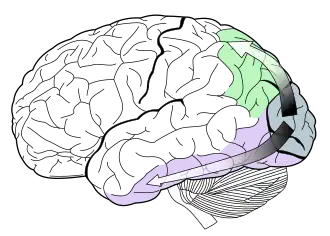

De cortex temporalis inferior vormt het eindpunt van de zogeheten ventrale route van het visuele systeem (zie afbeelding hiernaast). Deze is vooral verantwoordelijk voor de verwerking van kennis van objecten (‘wat-route’). Aangenomen wordt dat vroegere (dit wil zeggen dichter bij de visuele schors gelegen) stations in deze route betrokken zijn bij verwerking van elementaire visuele kenmerken (zoals: kleur, vorm), en latere stations bij verwerking van meer abstracte of betekenisvolle kenmerken (zoals: begrippen/categorieën) van waargenomen objecten. Neuronen in dit gebied reageren vooral op driedimensionale objecten.